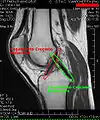

MRI

Both anterior cruciate ligament (ACL) and posterior cruciate ligaments (PCL) are hypointense on both T1 and T2 weighted images of MRI. However, some high signal striations are often seen at the distal part of the ACL, making ACL higher intensity than PCL on MRI scans.[17]